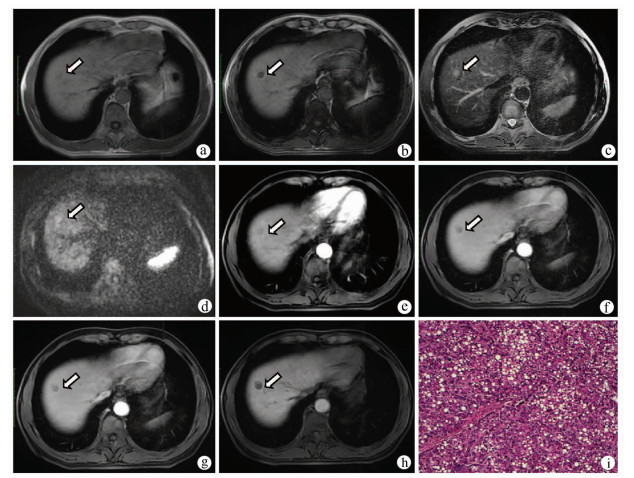

Consensus on imaging techniques and diagnostic criteria for hepatitis B virus related early hepatocellular carcinoma

Radiology of Infection Sub-branch, Radiology Branch, Chinese Medical Association, Committee on Radiology of Infection, Radiology Branch, Chinese Medical Doctor Association, Radiology Committee on Infectious and Inflammatory Disease, Chinese Research Hospital Association, Radiology of Infection Branch, Working and Treating Committee of HIV/AIDS and STD Association, Radiology of Infectious Disease Management Sub-branch, Infectious Disease Management Branch, Hospital Management Association in China, Beijing Imaging Diagnosis and Treatment Technology Innovation Alliance

2021, 37(4): 787-791. DOI: 10.3969/j.issn.1001-5256.2021.04.013

Abstract(1427) HTML (513) PDF (4471KB)(236)

Abstract:

The pathological diagnostic criteria for early hepatocellular carcinoma(eHCC)have been updated in 2009, but the imaging diagnostic criteria for eHCC have not yet been established by domestic or foreign academic organizations. Promoted by Radiology of Infection Sub-branch, Radiology Branch, Chinese Medical Association, associating with Committee on Radiology of Infection, Radiology Branch, Chinese Medical Doctor Association; Radiology Committee on Infectious and Inflammatory Disease, Chinese Research Hospital Association; Radiology of Infection Branch, Working and Treating Committee of HIV/AIDS and STD Association; Radiology of Infectious Disease Management Sub-branch, Infectious Disease Management Branch, Hospital Management Association in China; Beijing Imaging Diagnosis and Treatment Technology Innovation Alliance, this consensus was formed under the efforts of more than 40 experts from more than 10 domestic provinces and cities, so as to help related professional doctors in diagnosis of eHCC.